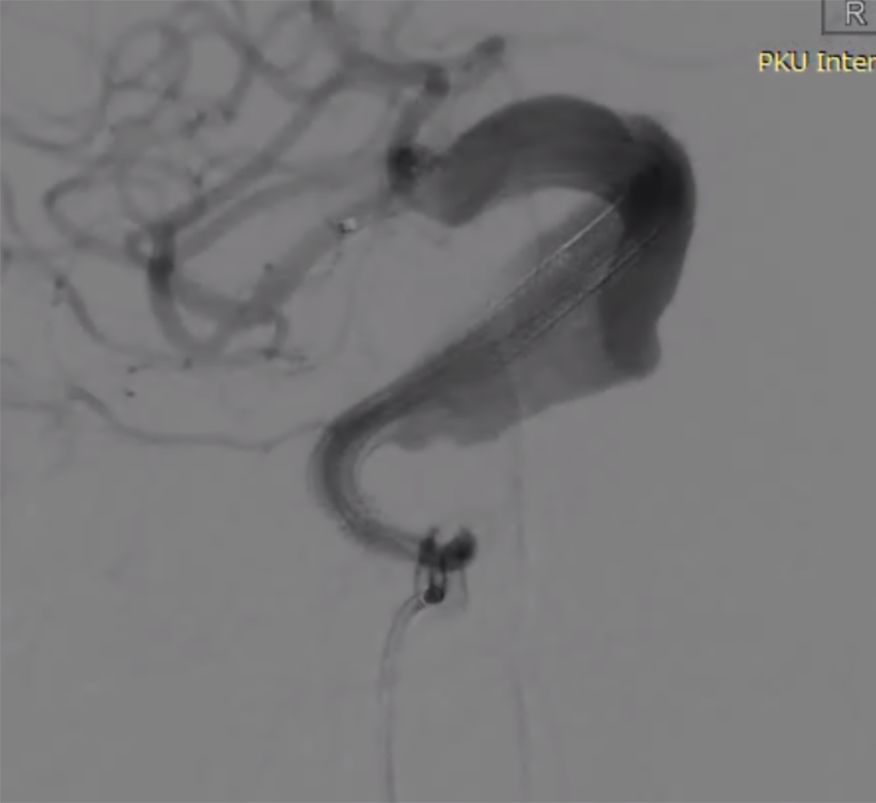

全身麻醉下右侧股动脉入路,造影选取工作位。

(1)Synchro微导丝携带Marksman支架管送入大脑中动脉,沿支架管送入3.5mm×35mmPED一枚,于M1段开始释放,可见释放后回缩明显,支架管在回收过程中支架再次短缩(图4)。

图4

(2)第二枚PED4.5mm×35mm桥接第一枚支架,释放过程中第一枚支架稳定,第二枚支架回缩同样明显(图5)。

图5

(3)第三枚PED 5mm×35mm桥接,可见近端已着陆于相对正常血管,但支架长度明显长于35mm,且近端血管转折处仍可见瘤样改变(图6)。

图6

(4)第四枚PED 5mm×35mm桥接第三枚支架,开始释放时贴壁不良,继续推出一段后支架展开,海绵窦垂直段支架展开形态欠佳,回收后推送形态不变,考虑存在狭窄(图7)。

图7